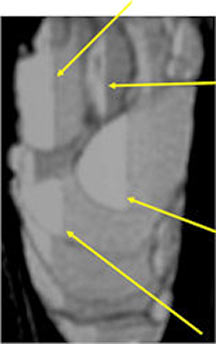

MRI/CT:

- Fluid-fluid levels secondary to cystic cavities filled with blood products. The sediment from blood products settle to the gravity dependent area of the cavity and the fluid component floats to top thus forming a fluid-fluid level.

- MRI and CT are also useful for demonstrating the local extent of the tumor and any soft tissue mass